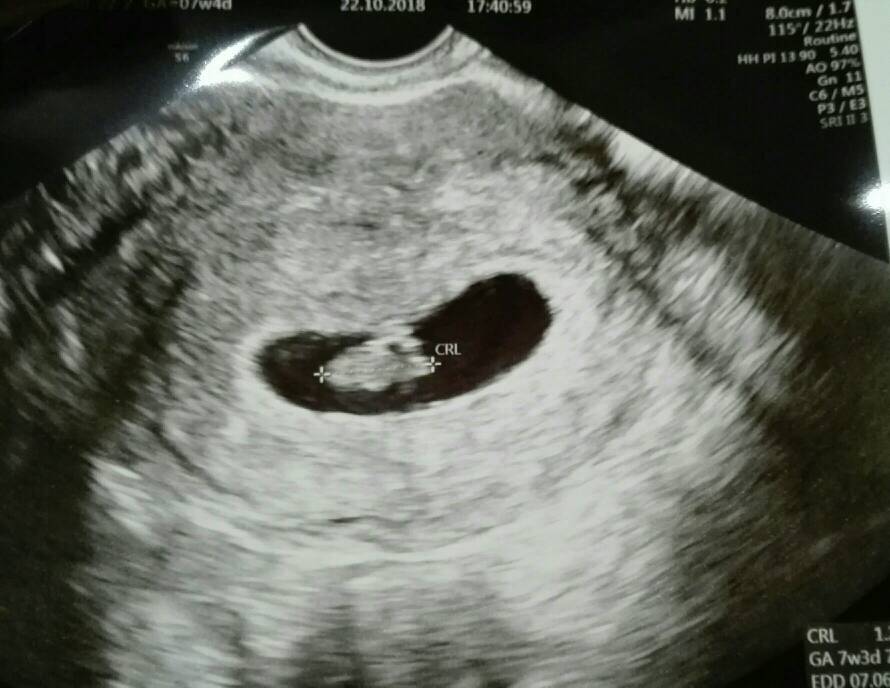

Hmm powiem ci ze ja sie na tych zdjeciach nie znam, wrzuce ci fotke jak to u mnie wygladalo w 7+3 [emoji57][emoji12]

Polowkowe mam za 8dni to moze juz wtedy sie dowiem (znow u innego gina, ciekawe co on stwierdzi [emoji23]) Hmm powiem ci ze ja sie na tych zdjeciach nie znam, wrzuce ci fotke jak to u mnie wygladalo w 7+3 [emoji57][emoji12]Zobacz załącznik 933528